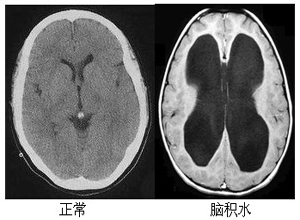

人腦是浸在“水”中的,這種“水”就是腦脊液。腦脊液包圍并支持著整個腦及脊髓。腦脊液是可以流動的,但如果因腦出血、外傷或感染等原因?qū)е履X脊液循環(huán)受阻或吸收障礙,腦脊液在腦室蓄積過多,就會導(dǎo)致腦積水。那么患了腦積水該怎么辦呢?